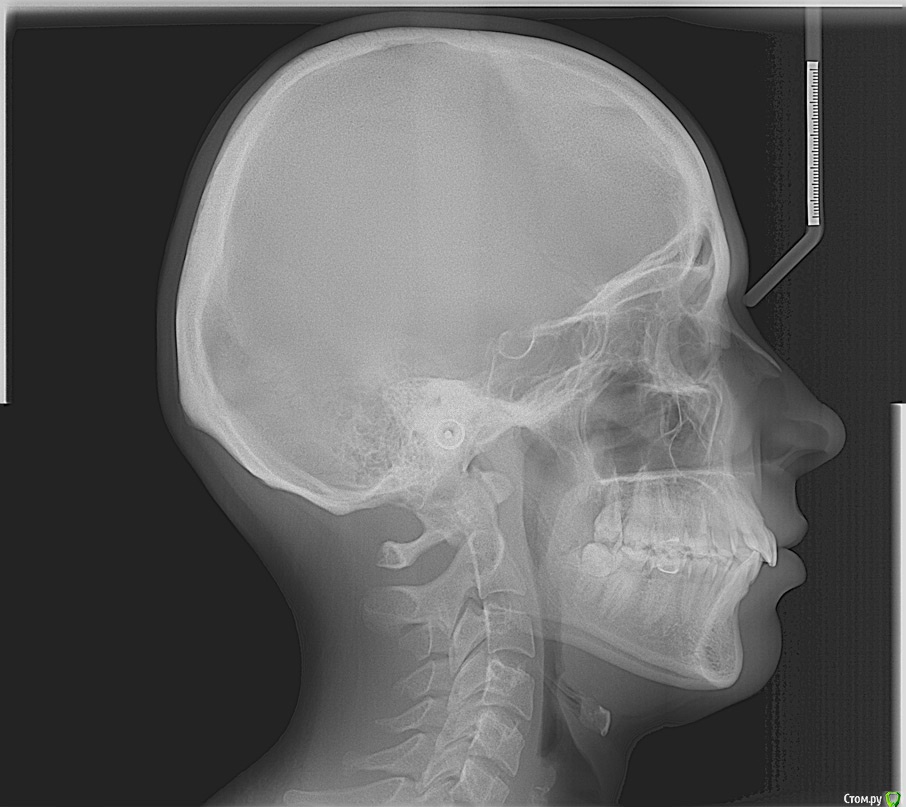

Здравстуйте! Мне 23 года.  У меня смещен центр верхней челюсти вправо и нижней влево. Больше беспокоит меня верх. На верхней челюсти, справа, отсутствует второй премоляр. На нижней клык слева. Премоляр мне в детстве удалили, он рос сверху зуба. Про нижний клык не помню. Проходила лечение не пластинке, не помню, к сожалению, почему. Очень хочу исправить эту ситуацию с зубами, но боюсь решиться, хочется получить гарантию от доктора, что все будет хорошо. Была на 3-х консультациях. На двух сказали что центр сместить нельзя. На одной доктор сказала, что нужно удалить сверху премоляр слева и снизу клык справа. Меня  интересует можно ли это исправить и каким методом, обязательно ли с удалением. Буду очень благодарна за помощь!!

post-43461-0-11136500-1433426624_thumb.jpg

post-43461-0-51373800-1433426625_thumb.jpg

post-43461-0-63657600-1433426626_thumb.jpg

post-43461-0-51033100-1433426627_thumb.jpg

post-43461-0-60355300-1433426628_thumb.jpg

post-43461-0-57034400-1433426629_thumb.jpg

post-43461-0-88100100-1433426630_thumb.jpg

post-43461-0-34744200-1433426632_thumb.jpg